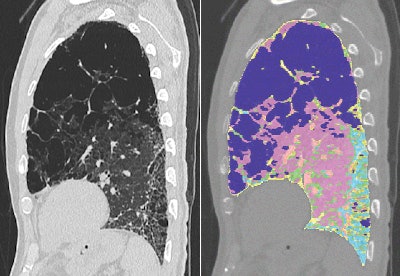

Images are of a 69-year-old man with idiopathic pulmonary fibrosis and emphysema. The patient was a former smoker (45 pack-years). Mean pulmonary artery pressure was 29 mm Hg, measured by right heart catheterization. Above left, computer-aided analysis showed 32.5% emphysema, 16% fibrosis, and 35.7% normal lung tissue volume. Above right and below, sagittal reformatted CT images show computer-aided segmentation results corresponding to the top left image. Pink = normal, dark blue = emphysema, light green = ground-glass opacity, light blue and yellow = fibrosis, dark green = trachea and bronchi, and orange = vessels. Images republished with permission from the American Roentgen Ray Society.

The lung volumes were examined on a computer-aided system that used CT attenuation values to distinguish fibrotic from normal, consolidated, and emphysematous regions on a PC. The automated tool extracts the lung from the CT images using a semiautomated threshold technique. Next, the bronchial trees and blood vessels are removed.

The algorithm categorized the lungs pixel by pixel, and then calculated the relative volume of each lesion to the CT lung volume as "normal(%)," "ground-glass opacities(%)," "consolidation(%)," "emphysema(%)," and "fibrosis(%)."